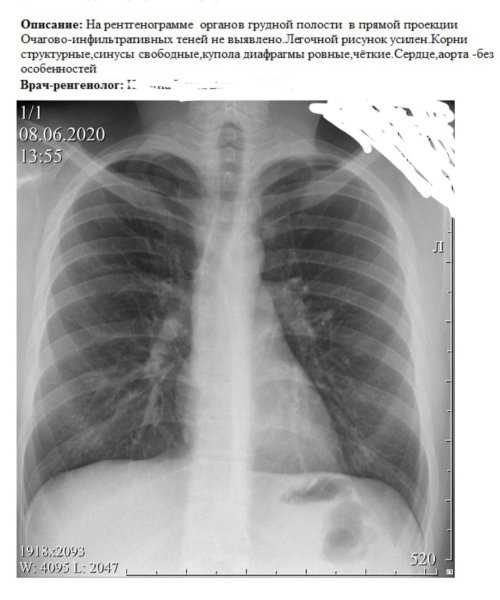

Рентгенограмма органов грудной полости в прямой проекции